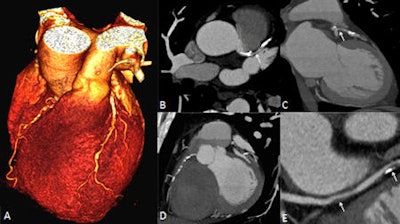

The image acquisition mode performed low-radiation (20% tube current) imaging over the majority of the cardiac cycle and applied full radiation only during a single adjustable phase. Full-radiation-phase images were used to assess cardiac morphology, while low-radiation-phase images were used to measure left and right ventricular function and mass.

The researchers compared quantitative CT measurements based on contiguous multiphase short-axis reconstructions from the axial CT data with short-axis steady-state free precession cardiac cine MRI. They also manually traced contours around the ventricular borders for calculation of left and right ventricular end-diastolic volume, end-systolic volume, stroke volume, ejection fraction, and myocardial mass for both modalities.